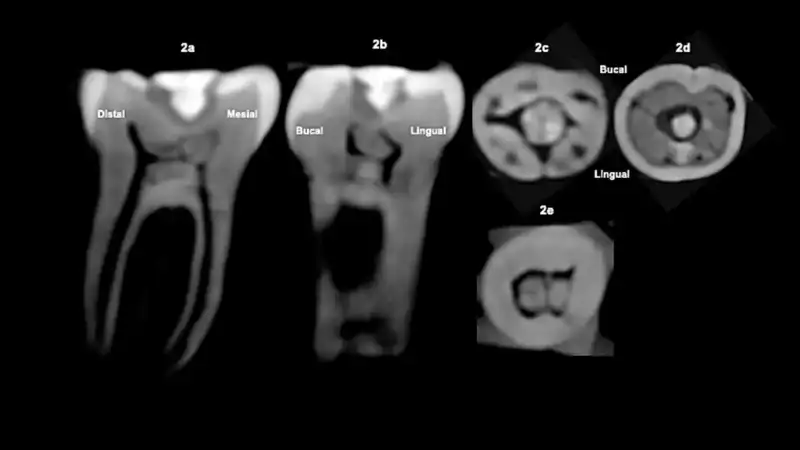

Esta diferencia es importantísima en arqueología, por eso el equipo recurrió a una técnica concreta, la tomografía computarizada de haz cónico (CBCT), que permite ver el interior del diente sin dañarlo. Lo que vieron fue que bajo la cavidad tallada para alojar la piedra, existían calcificaciones distróficas extensas en la cámara pulpar, lo que significa que había depósitos minerales producidos por la pulpa dental como respuesta al estrés y esta reacción biológica es imposible que ocurra en un diente ya ‘muerto’, de ahí que los autores hayan concluido que la incrustación se realizó cuando la persona aún vivía.

Otro detalle llamativo es la morfología de la incrustación. La piedra no es una simple placa; tiene forma de clavo, con una cabeza más ancha y un cuerpo corto cónico que encaja en el hueco tallado. Entre la piedra y las paredes aparece un material cementante radiolúcido. Y en las paredes internas se aprecian irregularidades y surcos radiales, interpretados como marcas de los instrumentos usados para perforar. Esa ‘firma’ técnica es indudable con respecto a lo que ya se sabía sobre los artesanos dentales mayas que eran especialistas capaces de taladrar esmalte con herramientas líticas y sellar incrustaciones con cementos orgánicos.